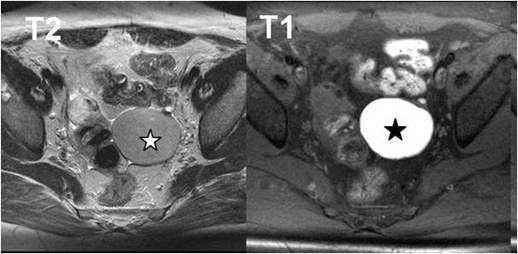

【110-1 醫學(六) 第72題】

35歲女性病患,主訴下腹痛,磁振造影檢查發現骨盆腔有囊狀病灶(星號),在T2加權影像(左圖)呈稍低訊號,T1加權影像(右圖)呈高訊號。其診斷為何?